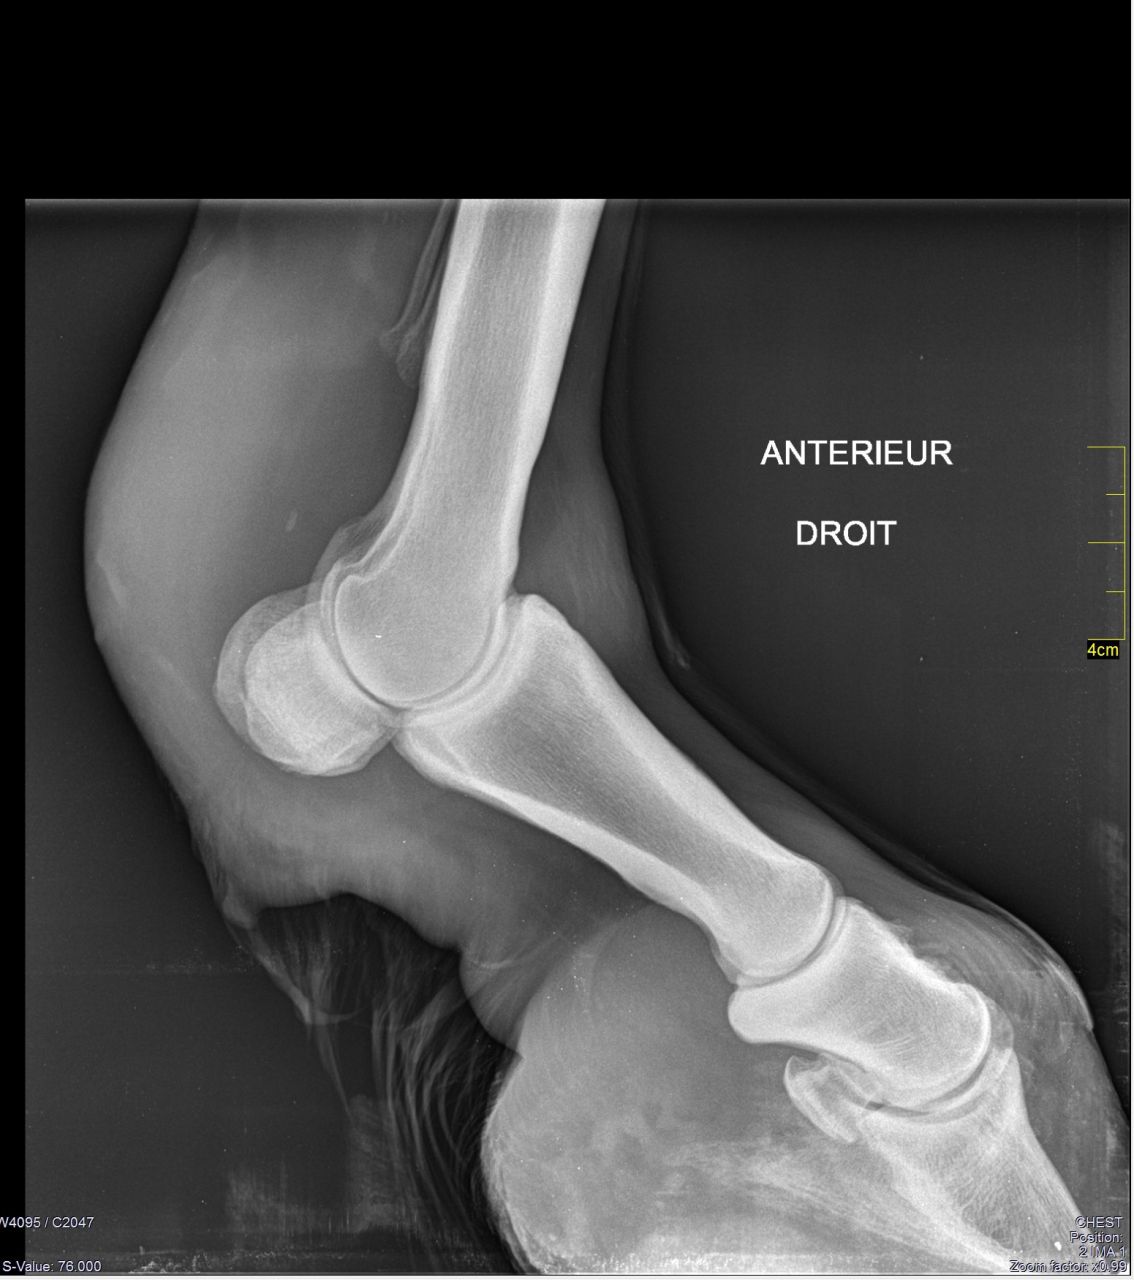

| Dire merci | Si seulement il pouvait être ici Regardez l'état de son antérieur droit ![]() |

| Dire merci | Oui il se déplace mais malheureusement de lui même il bouge pas beaucoup non pas qu'il peut pas mais il aime bien être dans la cabane. Il marche mais il est engourdi. Après quelques pas ça va mieux en général, sauf samedi il lui a fallut du temps pour être mieux. Mais une fois que je le rentre il recommence à avoir mal lève et pose l'antérieur à répétition. Dès que ça chauffe un peu il a mal à sa tendinite. Donc il marche oui, il a encore mal et les déplacements mal au début moins après et re mal quand ça a chauffé. Si ça n'a pas chauffé il a pas trop mal. |